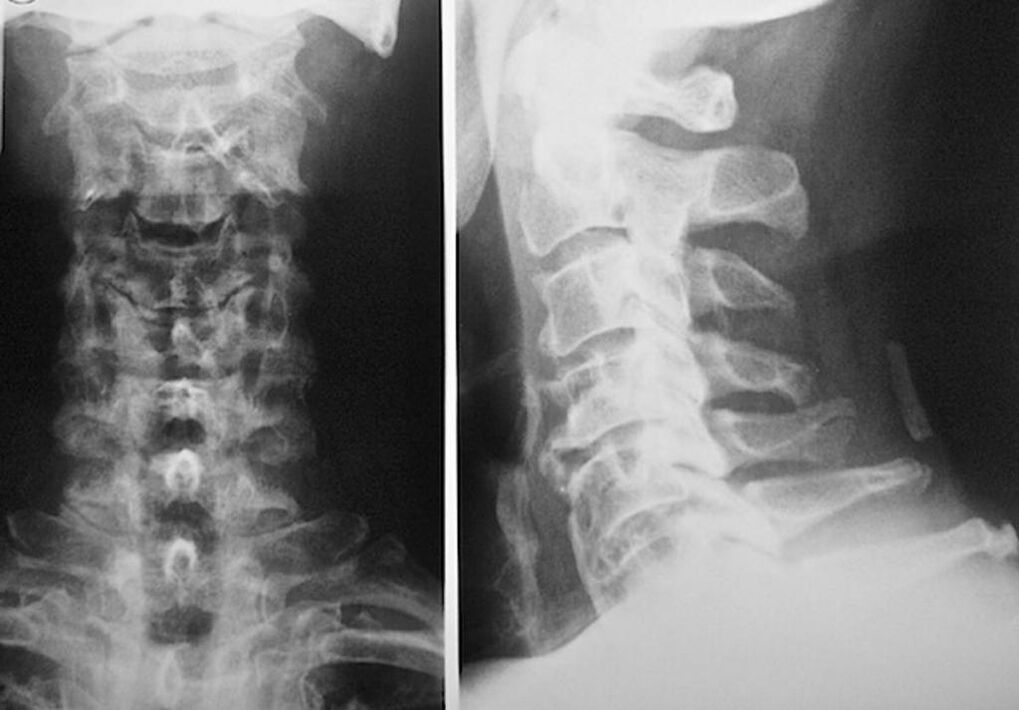

For the diagnosis and accurate assessment of the condition of the intervertebral discs, the following research methods are used:

- X-ray.

- CT scan.

- Magnetic Tomography.

- Ultrasound scan of the vessels of the neck.

Each of them is completely safe for health and carries no threat of excessive exposure. Diagnosis of osteochondrosis of the cervical vertebrae, the treatment of which will be carried out for the rest of life, can be made after a simple visual examination. Any orthopedist can do this easily. An exception is the first stage of the disease, when no visible pathologies of the cervical region are noted.